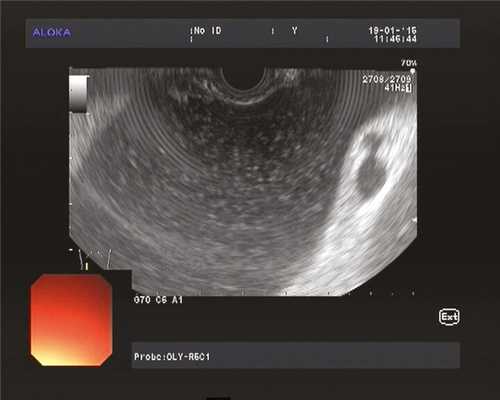

1. Проведение в желудок эхоэндоскопа OlympusGF-UE 160 и эндоскопическое ультразвуковое сканирование органов брюшной полости для определения зоны контакта стенки кисты со стенкой желудка (рис. 1). Рис. 1. Эхоэндоскопия и ультразвуковая визуализация панкреатической псевдокисты в теле поджелудочной железы (случай 1).